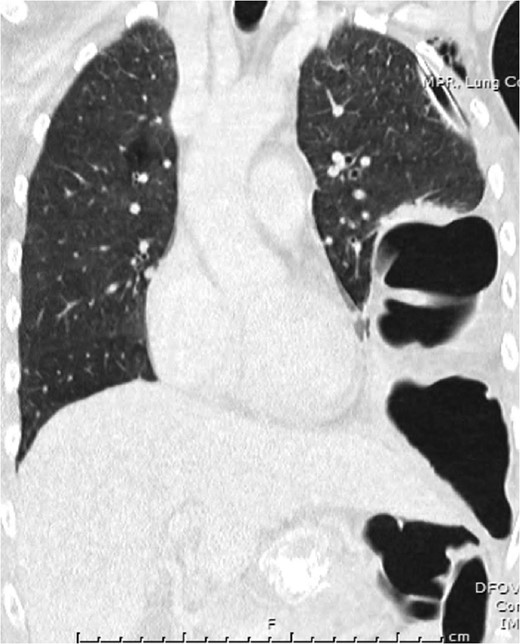

Video-assisted thoracoscopy (VAT) demonstrating a loop of transverse colon in the left hemithorax. Black asterisk (*) indicates a loop of transverse colon. Blue arrow indicates deflated left lung.